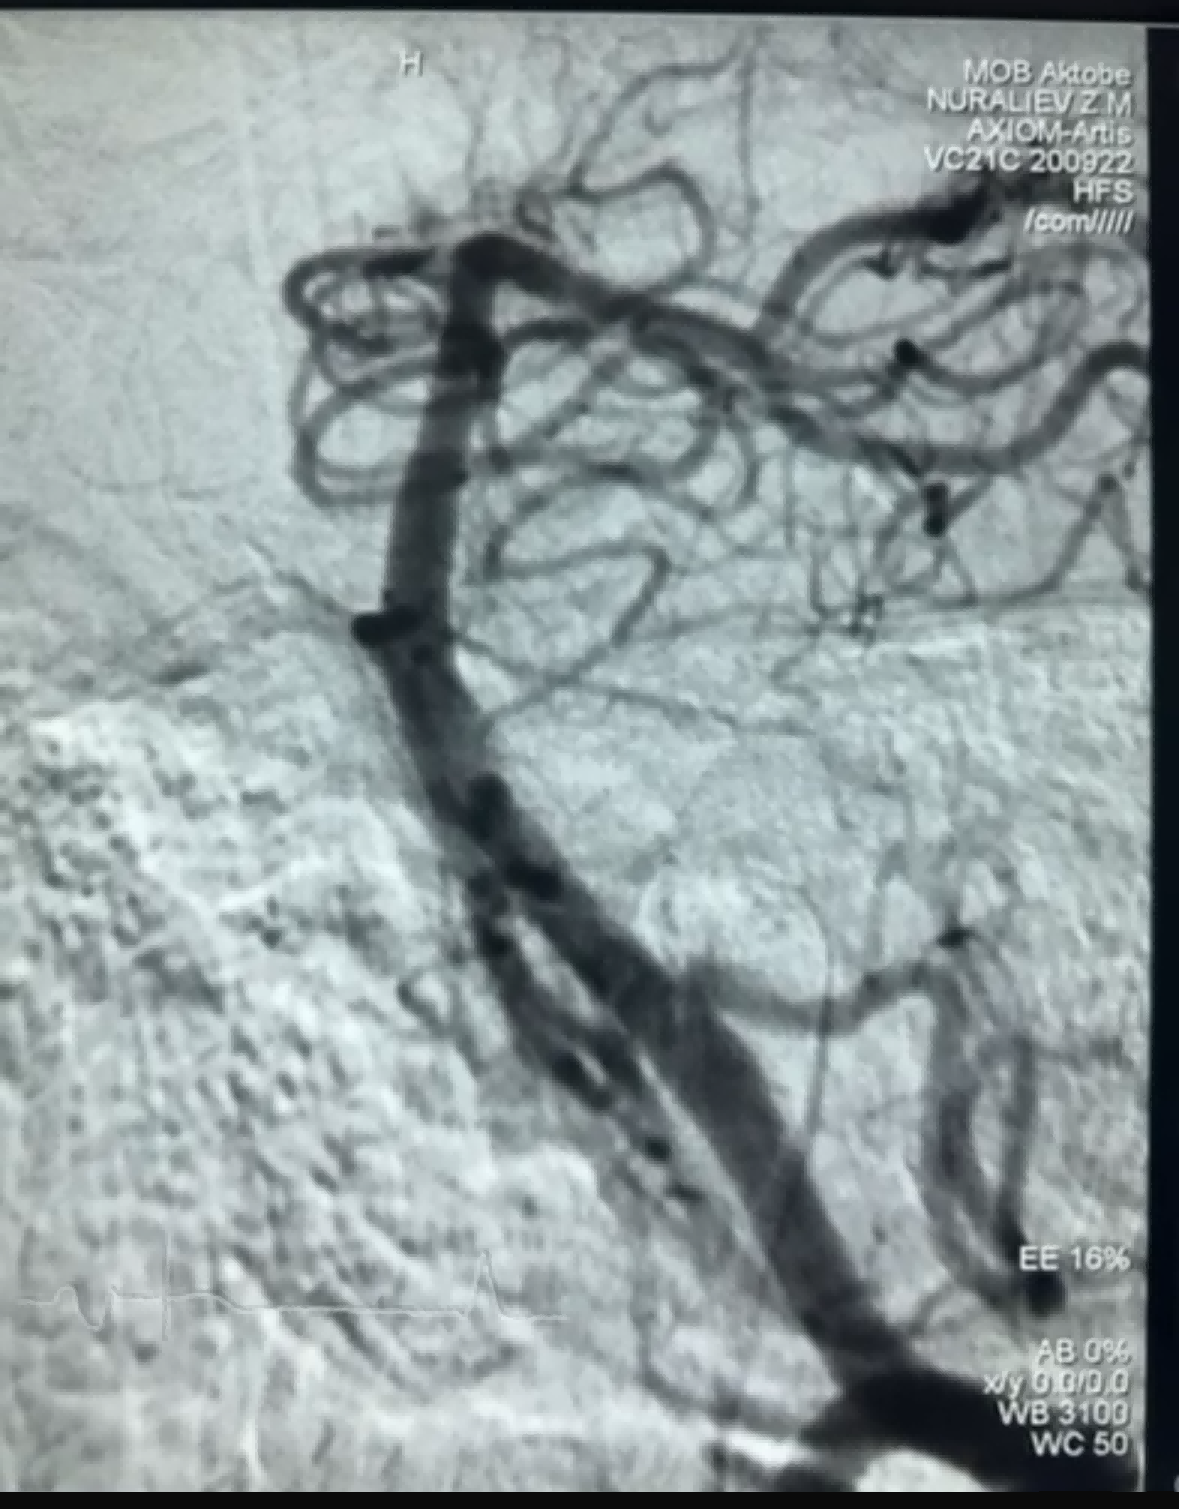

Recentment, hi va haver un cas de trombectomia amb èxit amb el Dredger Stent Retriever de NeuroSafe Medical Co., Ltd. El Dredger Stent Retriever té una punta suau no invasiva, que redueix molt el risc de danys a la íntima i té un forat únic amb forma especial. disseny que captura els coàguls de sang principalment mitjançant la fixació dels canvis de buit.